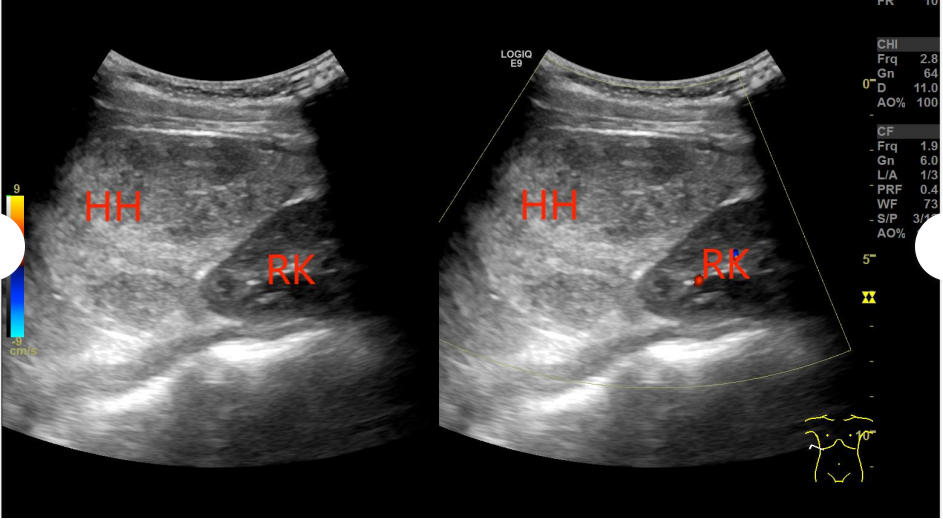

肝内小血管瘤二维及彩色血流图